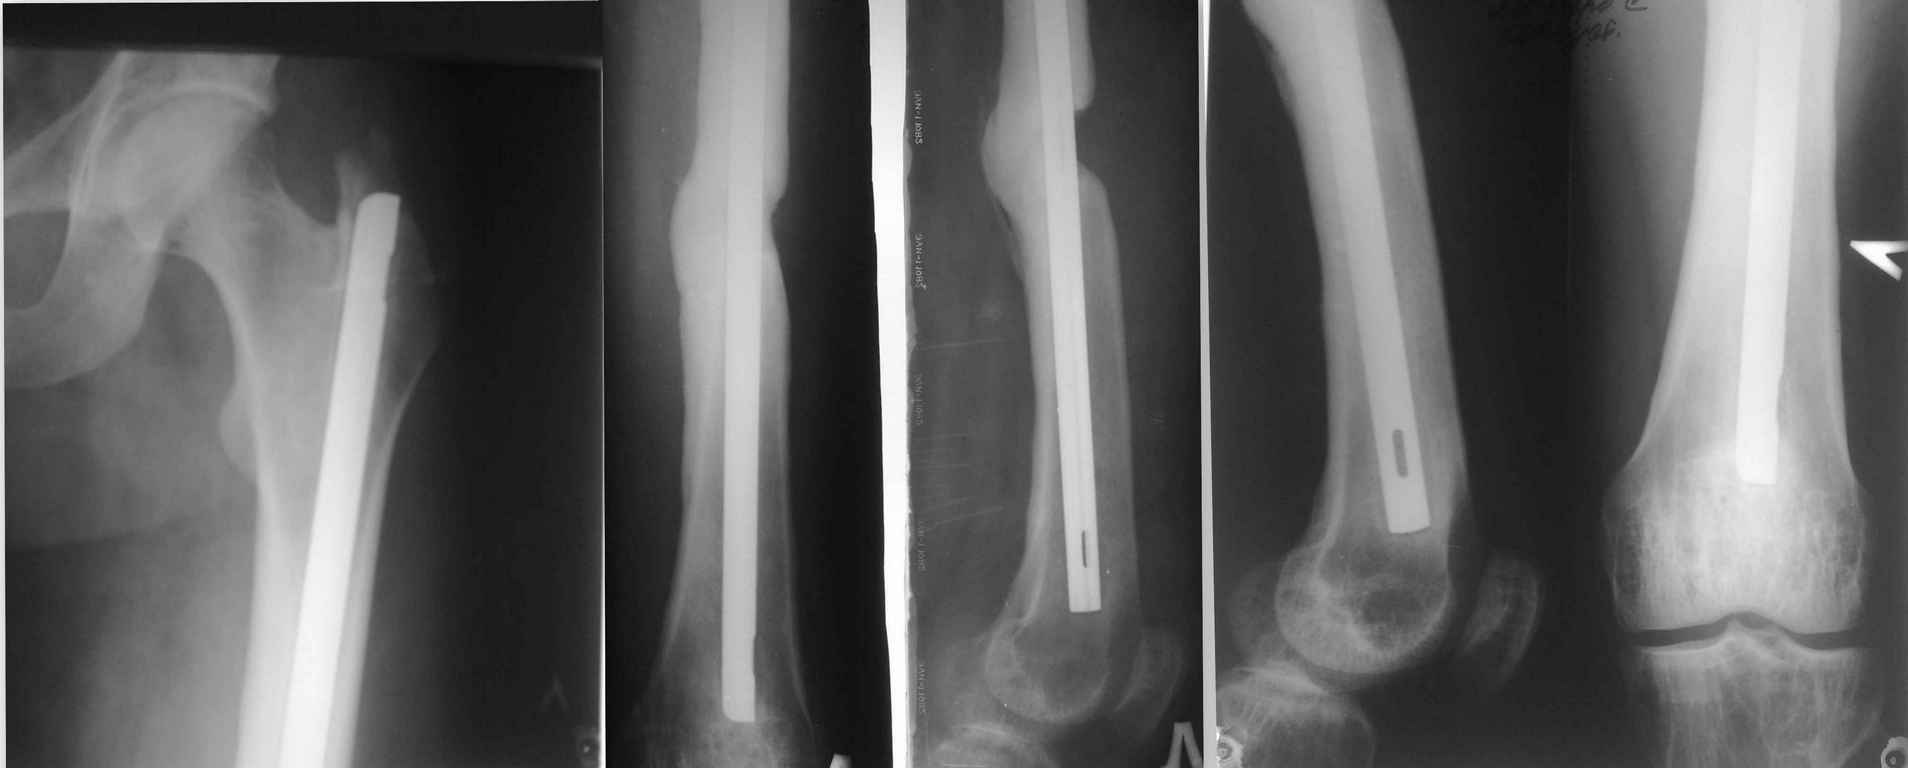

Здравствуйте Уважаемые коллеги! Просим совета. Есть больной 35 лет. Который получил сочетанную травму в результате ДТП более 2х лет назад. Оперирован на бедре МОС бедра штифтом, на голени накостной пластиной, которая через 2-3 мес. осложнилась развитием остеомиелита, попал затем к нам. Мы удалили пластину с Б/б кости и фиксировали в ВЧКО. Длительно лечился у нас с остеомиелитом б/б кости левой голени и по месту жительства, в общем, с голенью вроде всё в порядке на данный момент свищей нет. Бедро, сделанное в местной больнице ранее, тоже не беспокоило, но теперь начало, по снимкам бедра, сделанным ранее около года назад отмечается миграция стержня в бедре до 1.5 см. и появился на снимке дефект кости в области перелома. Ранее его не было. Кожных трофических нарушений нет. Металл не пальпируется. Больной настаивает на удаление металла. Как быть с учётом дефекта кости: удалять полностью штифт, с костной аутопластикой? БИОС?

Снимки эти последние! Ранее делались около года назад. Укорочение или удлинение конечности нет. Клиники нет! Просто хочет попрощаться со штифтом, даже настаивает. Просто если сравнивать их и новые есть небольшая миграция стержня дистально до 1,5 см не более! Снимки для сравнения сброшу. Спасибо за советы.

Прооперировали нашего пациента!Не одумался!Сделали ревизию верхнего конца штифта:Штифт подвижный легко удаляется,произвели ревизию место перелома с аутопластикой губкой. Заблокировали верхний конец штифта винтом.Послеоперационный период через 14 дней осложнился открытием свища на голени. Лечим!